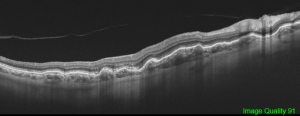

Fluorescein angiography cannot differentiate chorioretinal from choroidal folds, but the optical coherence tomography (OCT) patterns of the two are strikingly different although these are not completely singular entities. In cases of chorioretinal folds, OCT shows that the retina, RPE and choroid are all folded in a similar manner and maintain their normal relationships and apparently normal thickness, although a certain flattening of the inner retina can be seen along the crests, whereas choroidal folds correspond to undulations of the hyperreflective line corresponding to the RPE as well as the underlying choroid with a flat or nearly flat retinal surface with a variable retinal thickness variable, increasing in correspondence to the valleys and reducing in the crests. The retina, which has a softer structure, adapts itself to the wrinkling to preserve a flat inner surface.[19] The severity of choroidal folds have been staged on the basis of FA imaging. [28]

Linear signals of a decrease in choriocapillaris perfusion associated with choroidal folds can be seen on OCT angiography. [29]